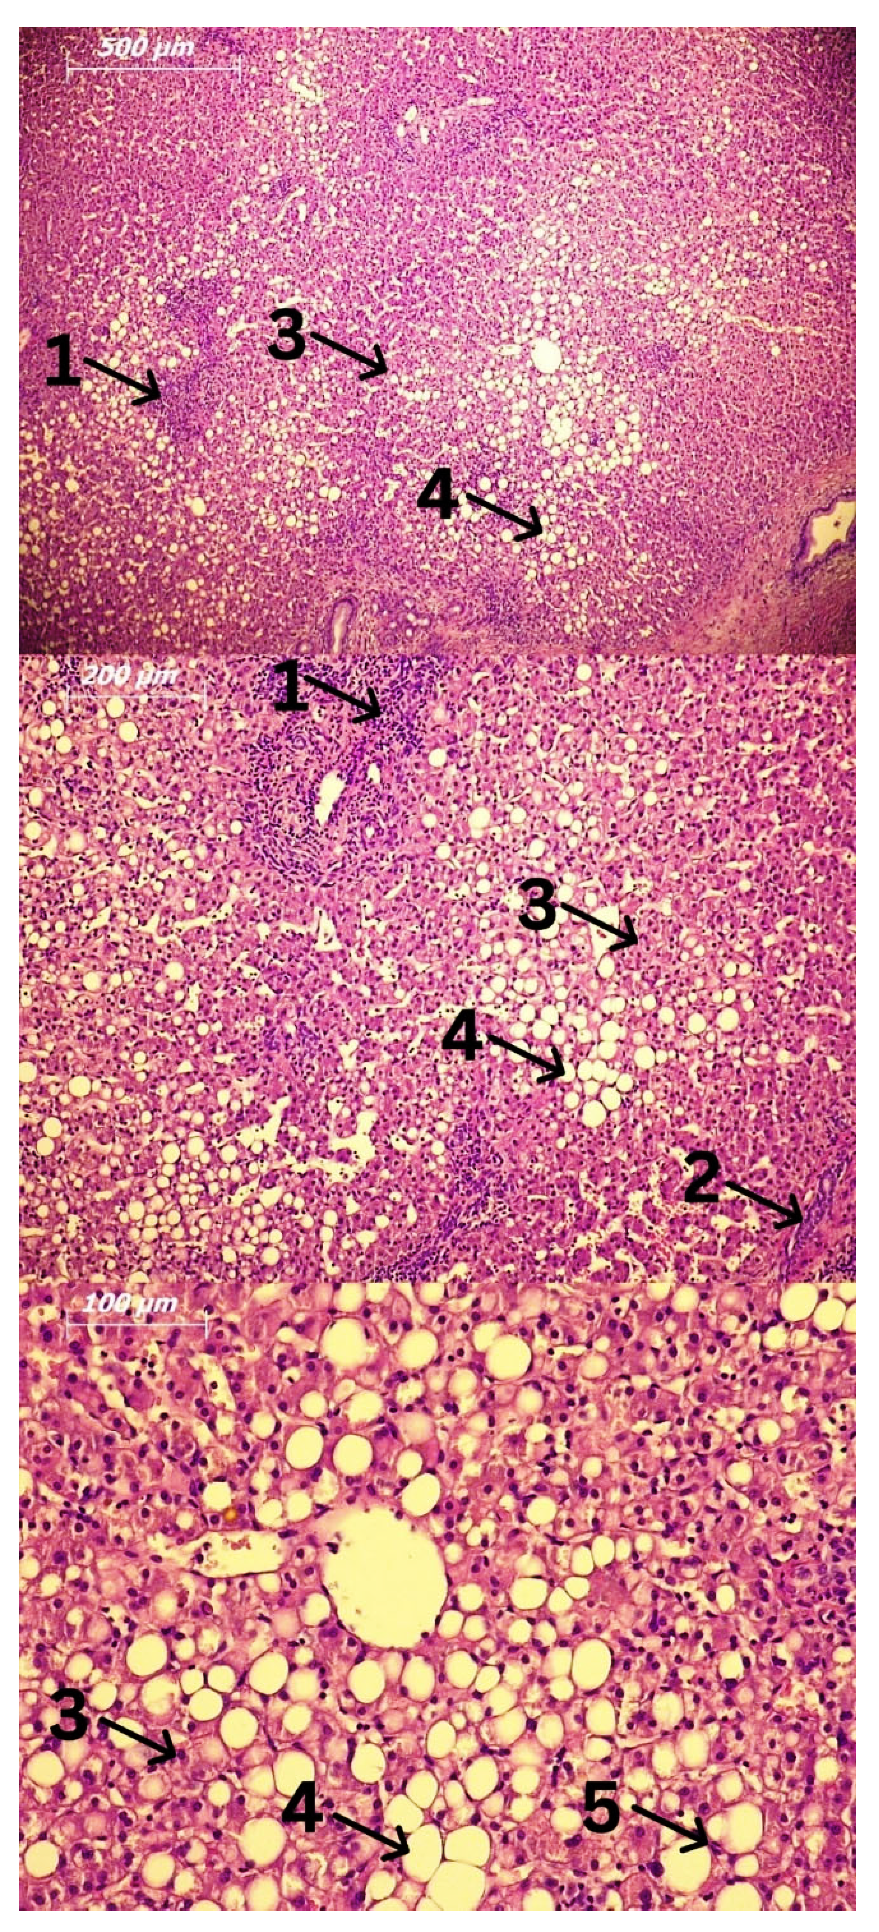

AFL is characterized by steatosis, primarily due to the accumulation of triglycerides in hepatocytes (Figure 2). They can be accumulated in the form of micro- and macro-vesicles and disrupt the architecture of the cell [4]. If AFL progresses, this process is related to the development of inflammation, consequent damage of hepatocytes, and a phenomenon called ballooning [23]. This progression occurs in 20–40% of people who chronically consume alcohol [19]. ASH usually progresses slowly over time and is characterized by the development of fibrosis in response to chronic inflammation. If the progression takes place quickly, alcoholic hepatitis (AH) may develop with or without liver failure [23]. Additionally, AH can occur as a result of worsening of other stages of alcoholic liver disease, not only steatohepatitis. Patients who develop AH have the fastest progression of fibrosis, and in them, apoptosis and necrosis of hepatocytes are more pronounced compared to ASH [23].

Figure 2.

Fatty liver biopsy. Hematoxylin and Eosin (H&E) staining. Legend: 1: Lymphocytes; 2: Focal necrosis; 3: Ballooned hepatocytes; 4: Fat accumulation; 5: Kupffer cells.